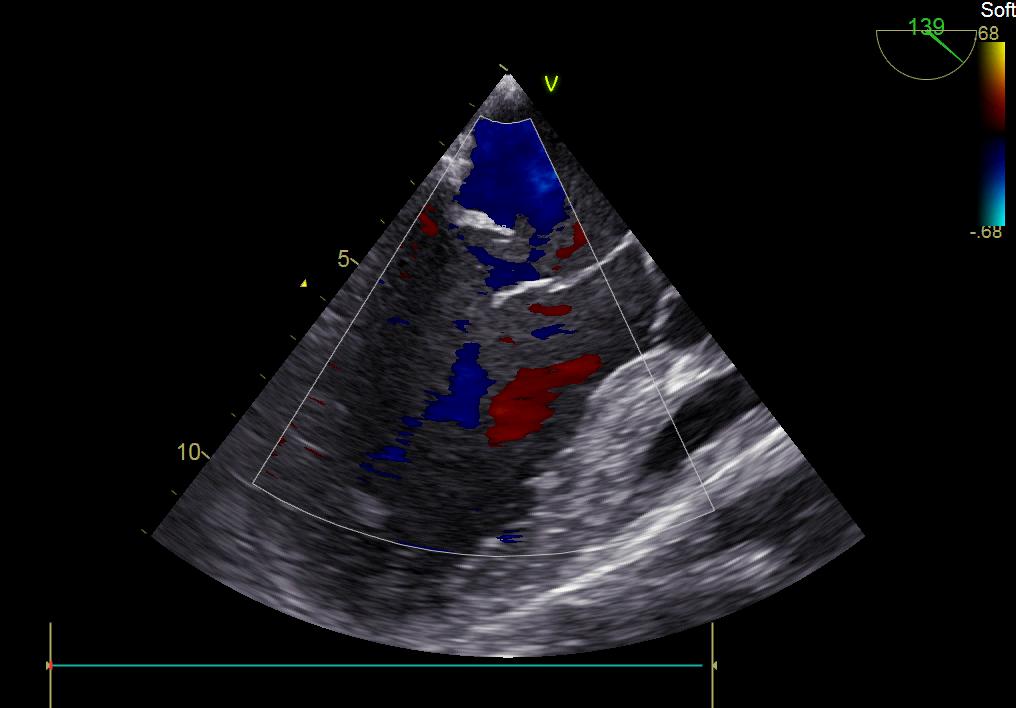

患者何某,42歲男性,因心功能不全入住我院心胸外科,心臟彩超提示二尖瓣后葉脫垂伴有重度返流及心臟擴(kuò)大,在迅速糾正心衰后,手術(shù)便提上日程,心胸外科廖金文主任多次組織全科及兄弟科室討論,在二尖瓣置換及成形術(shù)上,最終決定采取二尖瓣成形術(shù)。為保證手術(shù)安全,討論圍手術(shù)期各個(gè)細(xì)節(jié),所謂細(xì)節(jié)決定成敗,因?yàn)樾g(shù)前的細(xì)致全面,加上術(shù)中的一絲不茍及術(shù)后的精細(xì)化管理,患者術(shù)后恢復(fù)順利,健康出院,復(fù)查心臟彩超未見二尖瓣返流。

術(shù)前彩超

術(shù)后彩超